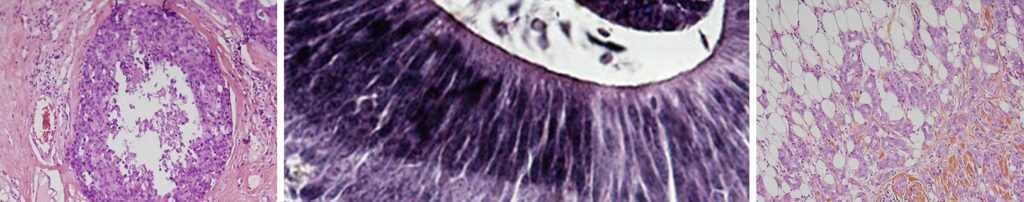

L’examen anatomopathologique

L’examen anatomopathologique au microscope des tissus prélevés est fondamental.

Il confirme le diagnostic de cancer du sein et précise les caractéristiques de la tumeur. Il établit une véritable « carte d’identité » du cancer, primordiale pour les choix thérapeutiques.

Ce que voit l’anatomopathologiste

2. Analyse définitive de la tumeur (en microscopie, après l’intervention)

- Analyse des caractéristiques de la tumeur, primordiale pour le traitement et le pronostic

L’analyse des cellules tumorales

Selon la ressemblance des cellules tumorales avec des cellules normales du sein, le médecin anatomopathologiste définit s’il s’agit d’un cancer différencié ou indifférencié. Plus une cellule cancéreuse ressemble à une cellule normale, plus elle est différenciée (ses caractéristiques sont proches de celles de la cellule normale du sein), moins elle est agressive.

En fonction de ce critère et d’autres observations, le pathologiste définit le grade du cancer (appelé grade « histopronostique d’Elston-Ellis »).

- Grade I : la tumeur est peu agressive.

- Grade II : la tumeur est intermédiaire. C’est le cas le plus fréquent.

- Grade III : la tumeur est agressive.

La détermination des marqueurs biologiques

L’anatomopathologiste analyse ensuite les marqueurs biologiques (biomarqueurs), à la surface des cellules cancéreuses. Ces caractéristiques biologiques permettent de préciser le type de cancer et de déterminer le traitement le plus adapté à la patiente.

- La détermination des récepteurs hormonaux. Si la cellule cancéreuse a des récepteurs hormonaux aux œstrogènes et/ou à la progestérone, la tumeur est dite hormonosensible. Un traitement approprié (hormonothérapie) sera alors proposé.

La détermination du statut HER2. Cette protéine intervient dans la prolifération cellulaire. En cas de surexpression de HER2 (trop grande quantité de cette protéine sur les cellules cancéreuses), un traitement postopératoire par anti-HER2 est possible (par exemple trastuzumab, dont le nom commercial est Herceptin®, pertuzumab, …). On parle de « thérapie ciblée », car ce médicament agit sélectivement sur les cellules cancéreuses porteuses du récepteur.

La mesure de l’index de la protéine Ki-67. Cette protéine est un marqueur de prolifération cellulaire. Comme pour les autres biomarqueurs, son étude permet de caractériser la cellule, et peut aider au choix de la meilleure stratégie thérapeutique.